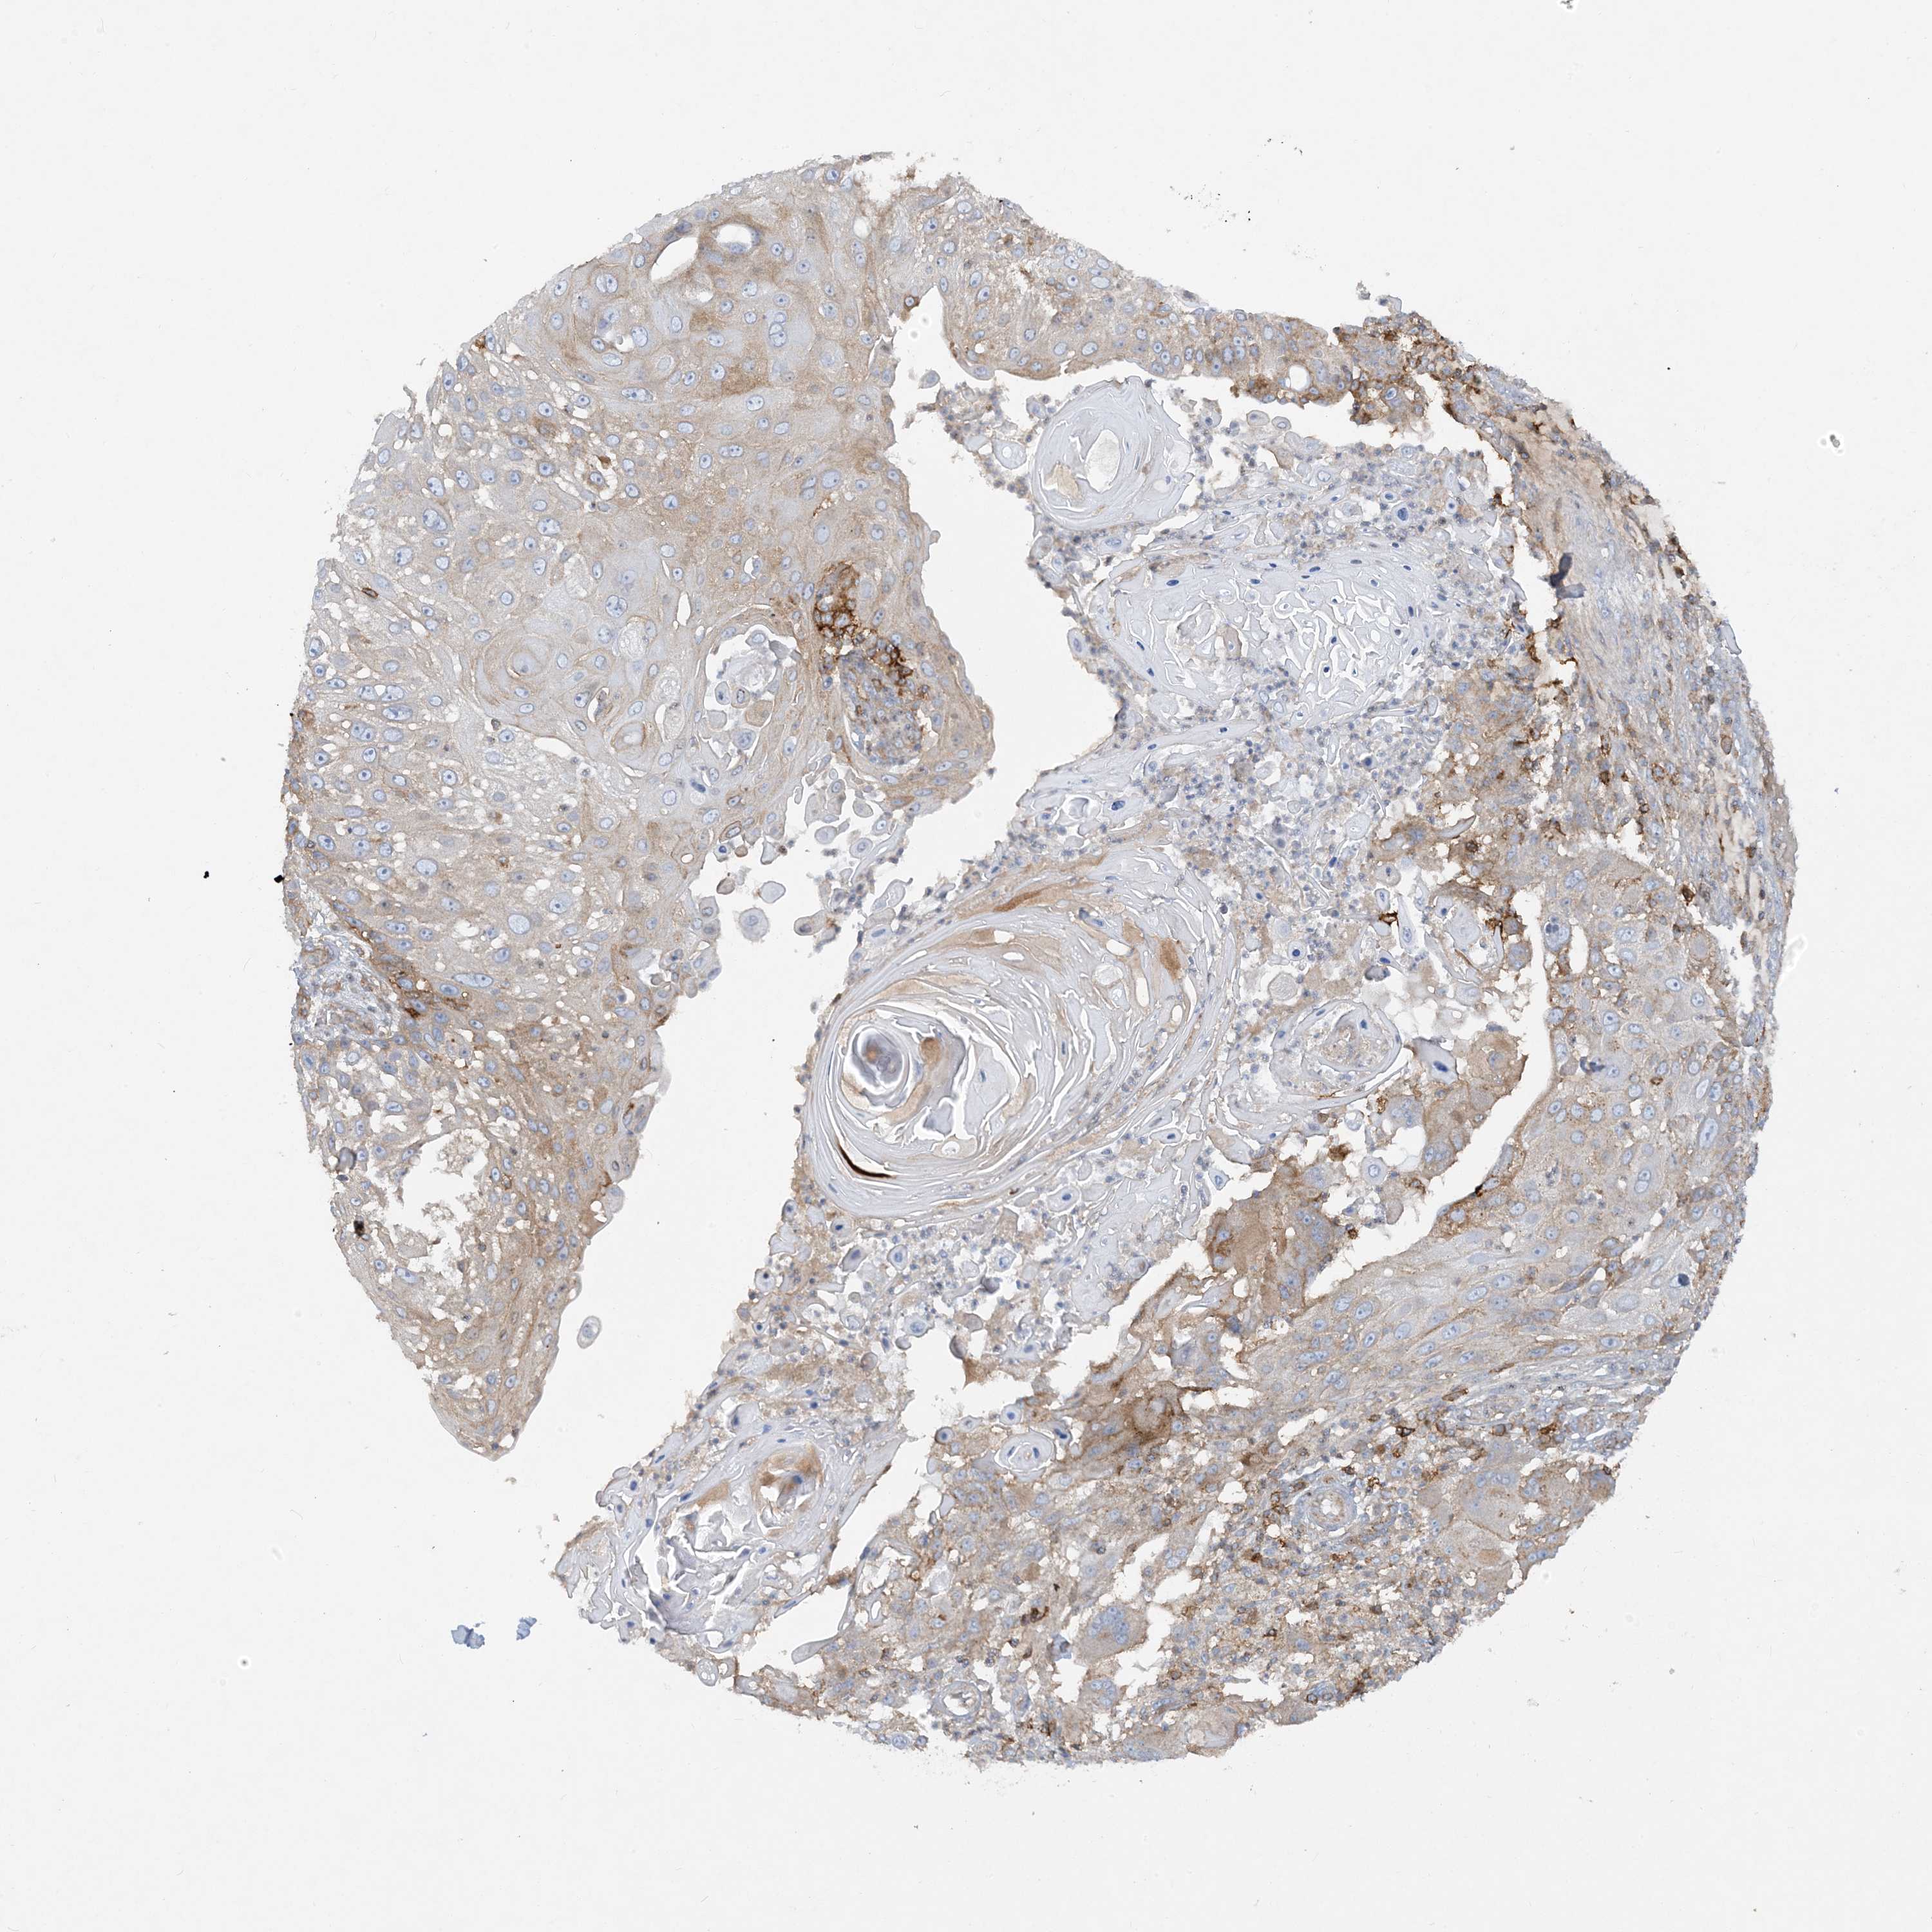

SKIN CANCER - Protein expressioni

A mouse-over function shows sample information and annotation data. Click on an image to view it in a full screen mode. Samples can be filtered based on level of antibody staining by selecting one or several of the following categories: high, medium, low and not detected. The assay and annotation is described here.

Antibody staining in the annotated cell types in the current human tissue is reported as not detected, low, medium, or high, based on conventional immunohistochemistry profiling in selected tissues. This score is based on the combination of the staining intensity and fraction of stained cells.

Each image is clickable and will lead to virtual microscopy that enables deeper exploration of all samples and also displays staining intensity scores, fraction scores and subcellular localization as well as patient and tissue information for each sample.

Antibody HPA031454

Staining

High

Intensity

Strong

Quantity

>75%

Location

Cytoplasmic/membranous

Basal cell carcinoma